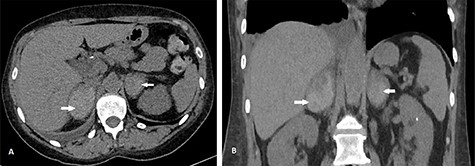

She had a non-contrast computed tomography (CT) of the abdomen to rule out urolithiasis. This showed features of right-sided pyelonephritis and small bilateral renal calculi but no ureteric calculi or hydronephrosis. BAH was confirmed on her triple phase renal CT scan (Fig. 1). She was started on intravenous fluids and broad-spectrum antibiotics (IV temocillin and gentamicin) to cover for suspected pyelonephritis. Her warfarin was held initially, and she was given vitamin K. Following advice from the hematologists, she was subsequently started on treatment dose of enoxaparin, but her platelet count started to decline, and this was changed to fondaparinux. On her second day on admission, she developed adrenal insufficiency evidenced by persistent hypotension, hyponatraemia of 122 mmol/L (reference range 133–146 mmol/L) and hypocortisolaemia of 40 nmol/L (reference range 100–500 nmol/L). She received intravenous hydrocortisone which was converted to oral steroids after 24 h. Her sodium level normalized by Day 8 of admission. Following 3 days of intravenous antibiotics, she was changed to oral amoxicillin, which was continued for 7 more days.

CT scan showing axial (A) and coronal (B) views of BAH (arrows). The right adrenal hemorrhage measured 35 × 52 mm axially and the left adrenal hemorrhage measured 40 × 33 mm.